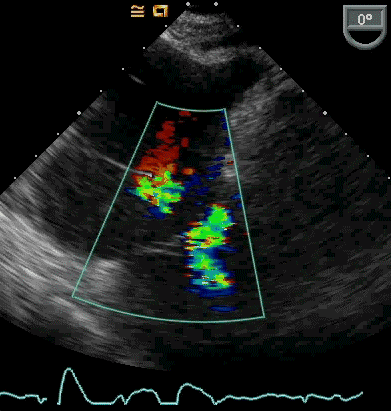

当然,这两型房间隔缺损通过经食管超声心动图可以清楚显示,但在没有